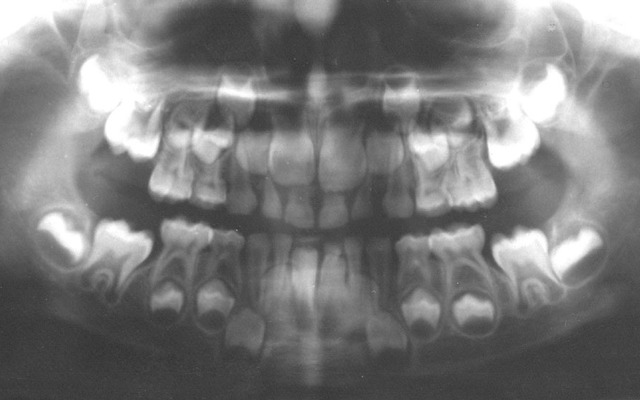

A panoramic radiograph is a panoramic scanning dental X-ray of the upper and lower jaw. It shows a two-dimensional view of a half-circle from ear to ear.

The X-rays use small amounts of radiation. Panoramic X-rays show a broad view of the jaws, teeth, sinuses, nasal area, and temporomandibular (jaw) joints. These X-rays show problems such as impacted teeth, bone abnormalities, cysts, solid growths (tumors), infections, and fractures